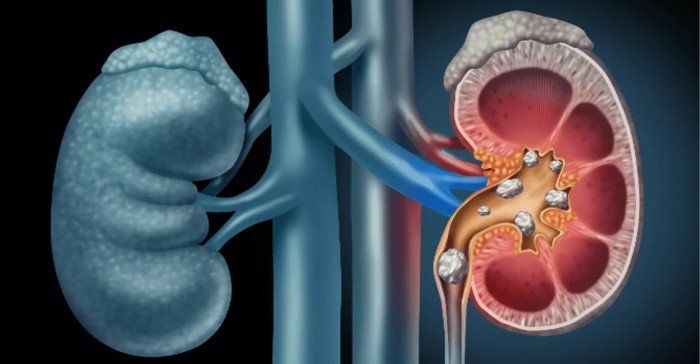

تم تطوير BMVision، وهو اسم الأداة، في جامعة تارتو، وتقييمه سريريًا في مستشفى جامعة تارتو. وقد حصلت على موافقة CE في يناير 2024، مما يسمح بتسويقها واستخدامها في جميع أنحاء أوروبا. يساعد هذا النظام في تحليل صور التصوير المقطعي المحوسب (CT) للكلى، مما يتيح لأطباء الأشعة تحديد وتقييم الأورام بشكل أسرع وأكثر دقة.

يعتبر سرطان الكلى من الأمراض المتزايدة الانتشار على مستوى العالم، والكشف المبكر عنه يلعب دورًا حاسمًا في تحسين فرص العلاج والشفاء. يُعد التصوير المقطعي المحوسب (CT) من أهم الأدوات المستخدمة في تشخيص هذا النوع من السرطان، ولكنه يتطلب وقتًا وجهدًا كبيرين من أطباء الأشعة لتحليل الصور بدقة.

تعتمد BMVision على تقنيات التعلم الآلي، وهي فرع من فروع الذكاء الاصطناعي، لتحليل صور التصوير المقطعي المحوسب (CT) للكلى. تقوم الأداة بتدريب نماذجها على مجموعة كبيرة من الصور التي تم تشخيصها مسبقًا، مما يمكنها من التعرف على الأنماط التي تشير إلى وجود أورام، سواء كانت خبيثة أو حميدة.

وفقًا لدراسة نشرت في مجلة Communications Medicine، قام أطباء بمراجعة 200 فحص CT بطريقتين: الأولى باستخدام الأداة الجديدة، والثانية بالطريقة التقليدية. أظهرت النتائج أن استخدام BMVision قلص الوقت اللازم لتحديد وقياس الأورام الخبيثة بنحو الثلث، مع تحسين دقة القياس وزيادة التوافق بين آراء الأطباء.